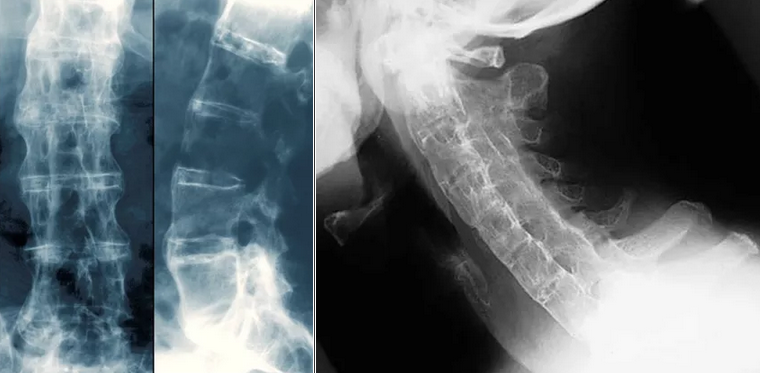

Рисунок 5. Слева и в центре: "Бамбуковый позвоночник" при анкилозирующем спондилите. На данном рентгеновском снимке позвоночника пациента с АС между позвонками выявляется вновь образовавшаяся костная ткань (ярко-белого цвета). В местах, где слияние позвонков завершено, наблюдается формирование «бамбукового позвоночника». Справа: "Бамбуковый позвоночник" при анкилозирующем спондилите. На рентгенограмме шейного отдела позвоночника в боковой проекции показано окостенение шейного отдела позвоночника у пациента с тяжелым давним АС. Позвоночник полностью анкилозирован благодаря синдесмофитам, слитым фасеточным (апофизарным) суставам и параспинальной кальцификации связок.